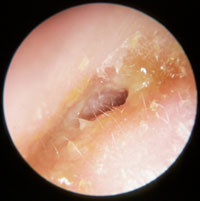

Bullous myringitis (type of AOM)

Can be mistaken for herpes zoster oticus (Ramsay Hunt)

The tympanic membrane shows erythematous changes with visible isolated hemorrhagic infiltrates (dark spots)